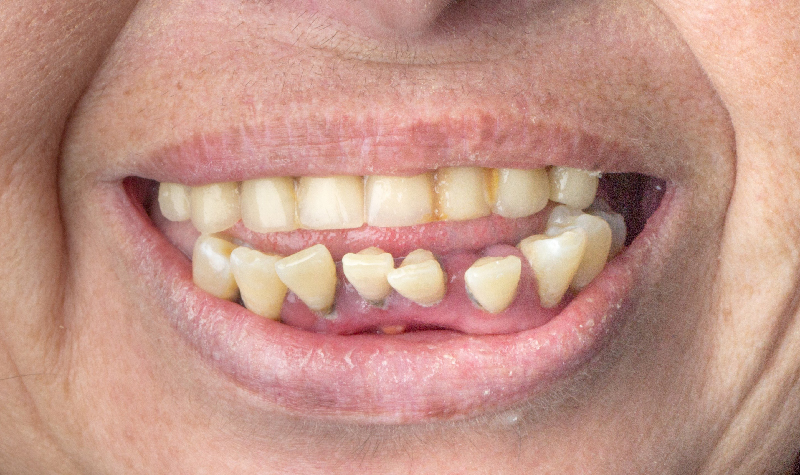

Rehabilitación oral total de alta complejidad con cerámicas sobre dientes e implantes.